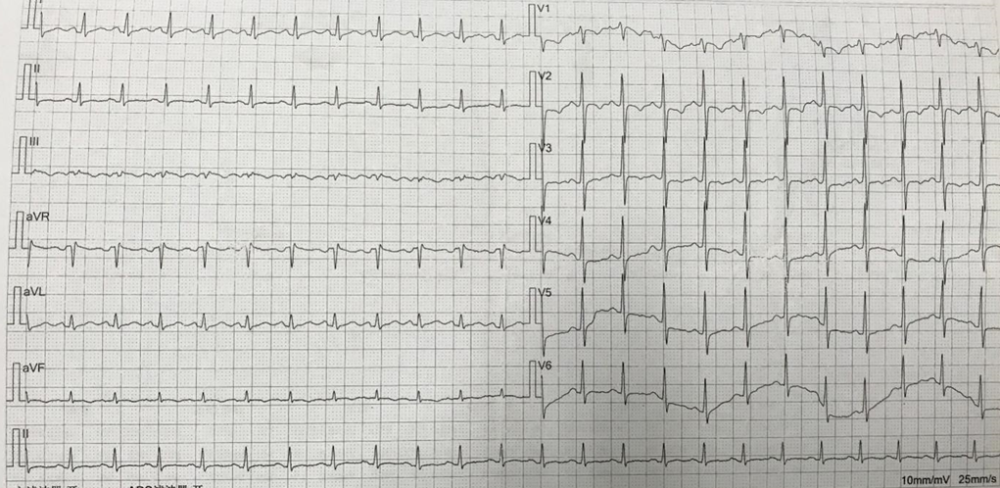

急性正后壁心肌梗死心电图

nejm心电病例速递:后壁心肌梗死

患者入院心电图

后壁心梗心电图表现